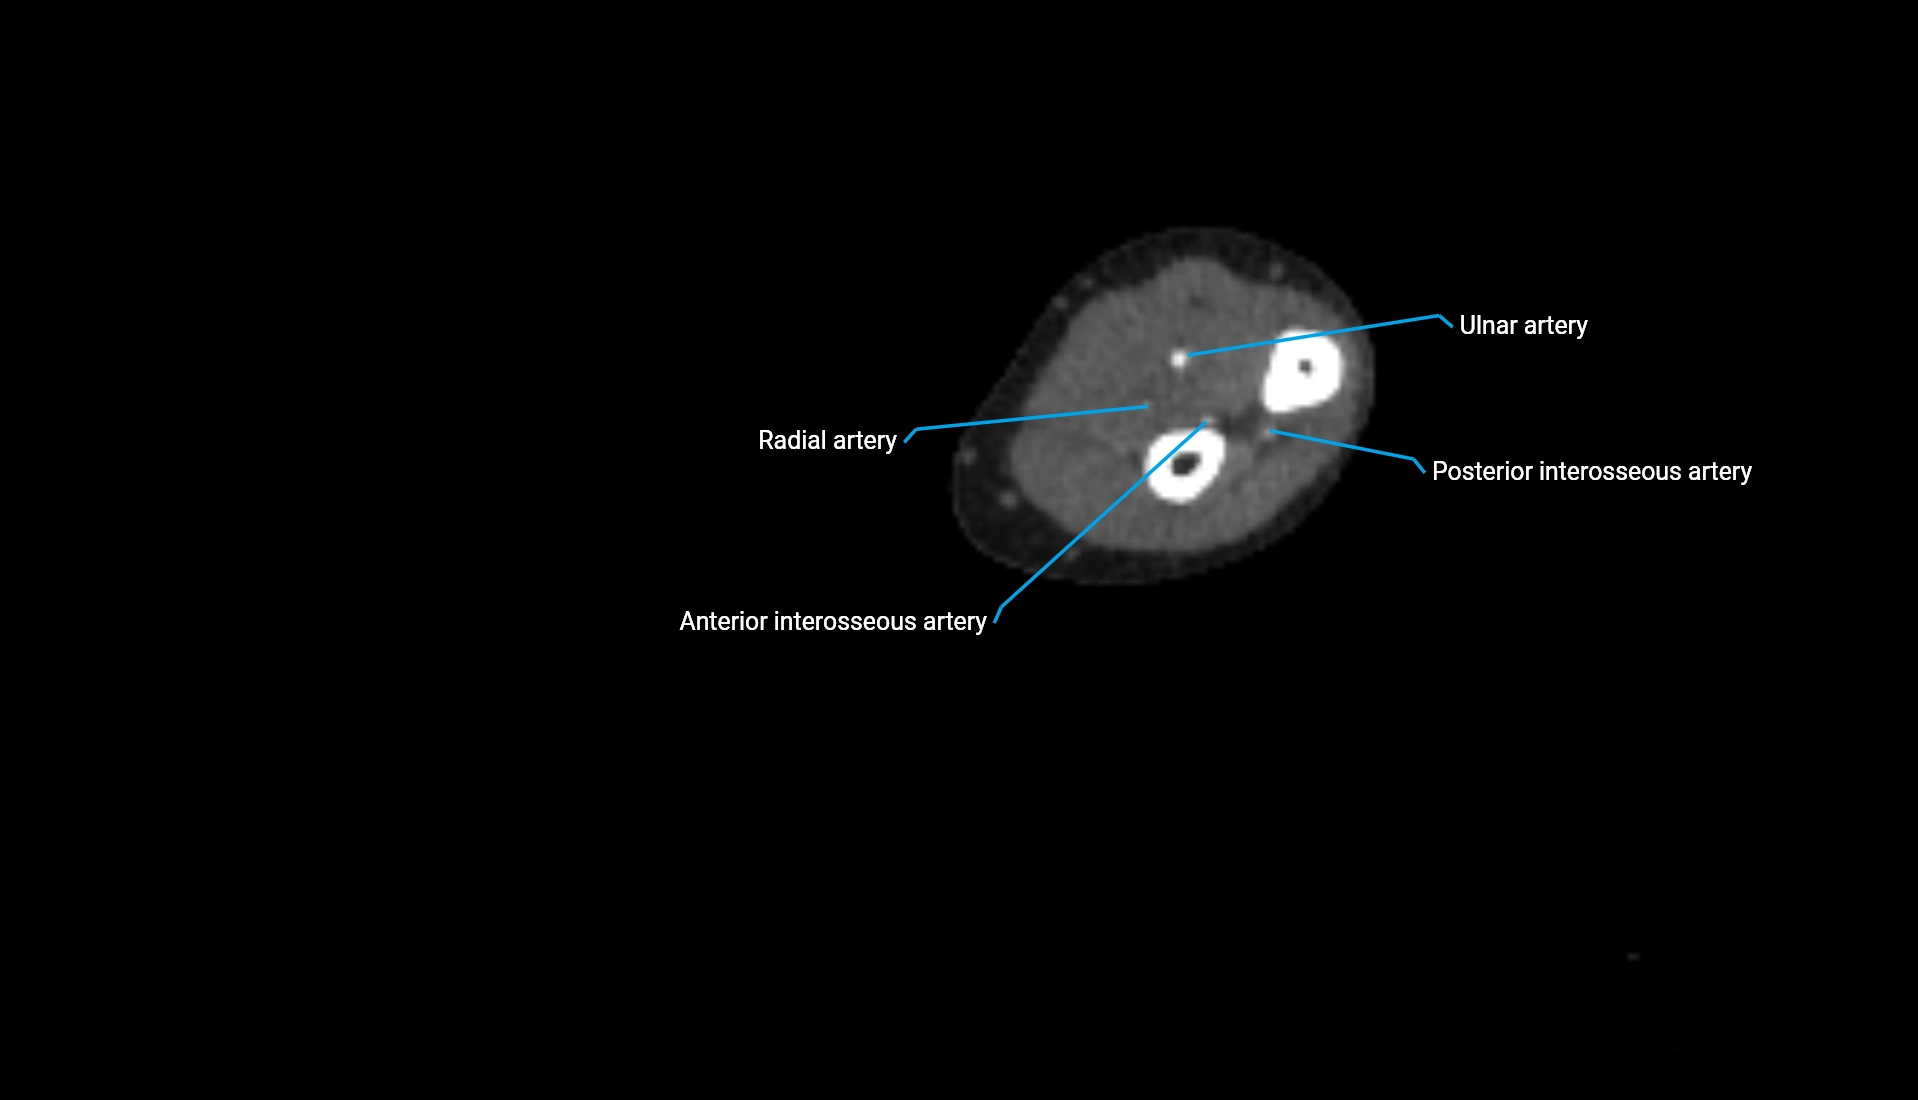

CT Appearance

Non-Contrast CT:

• Cortex: High-density, sharply defined

• Subchondral bone: Dense cancellous matrix

• Articular surface: Smooth concave contour articulating with the capitellum

• Excellent for evaluating bone integrity, alignment, and subtle fractures

Post-Contrast CT:

• Bone: No enhancement

• Joint capsule and synovium: Mild enhancement outlining the joint

• Improves contrast between soft tissues and bony margins

• Useful in detecting subtle joint abnormalities or postoperative changes